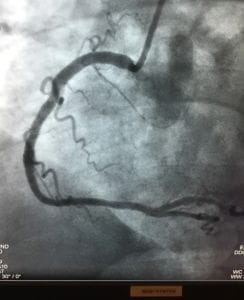

The procedure was uneventful and successful. My right coronary artery was almost completely occluded. My left anterior descending artery was 80% narrowed. Both needed treatment, and luckily both were amenable to stenting. Two stents were deployed and my chest felt lighter immediately. I felt younger and running again even crossed my mind. But first, I realized how stupid I had been … what if I had dropped dead like my father?